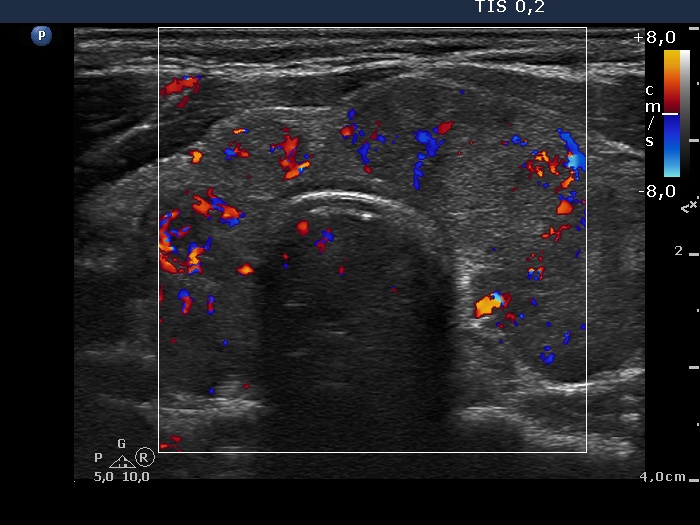

The thyroid, transverse scan, color Doppler mode. The vascularization is not specific.

Right lobe, longitudinal scan